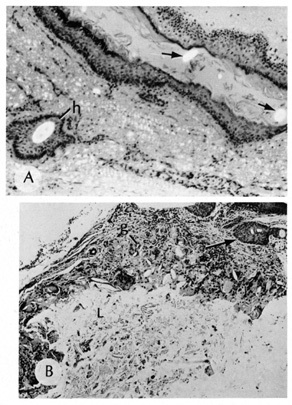

Dermoid Cysts

Dermoid cysts are usually present at birth and commonly occur around the eyes. They may be adherent to the periosteum. Dermoid cysts are believed to result from sequestration of skin and its appendages along embryonic lines of closure and, thus, are commonly found at the frontozygomatic suture.

Histologically, dermoid cysts are lined by epidermis possessing various mature appendageal structures (Fig. 22). These include hair follicles with terminal hairs, sebaceous glands, eccrine glands, and, occasionally, apocrine glands.

Fig. 22. A. Dermoid cyst shows hair follicle (h) and hair shaft (arrows) in cyst lumen. B. Dermoid cyst has skin appendages in cyst wall (arrow), is lined by stratified squamous epithelium, and contains desquamated keratin in its lumen (L). There is a granulomatous inflammatory infiltrate (g) due to rupture of cyst. (From Yanoff M, Fine BS: Ocular Pathology, 3rd ed. Philadelphia, JB Lippincott, 1989, 186.)